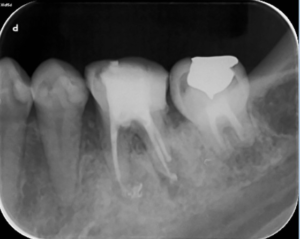

根の治療9か月後のレントゲン写真です。矢印の根の先の骨の溶けている部分は無くなっています。この後、仮歯からジルコニア製のかぶせを装着されました。

治療後

奥歯は複数の根があり、根の病気になるとなかなか治癒させるのが難しいです。

しかし、精密根管治療でマイクロスコープを用いて、目視下で原因となる根の中の汚れを除去し、抗菌性のある材料で根の中をつめるとこのように治癒に導くことができます。治療に伴い症状が全くなくなったため、患者様はとても喜ばれておられました。